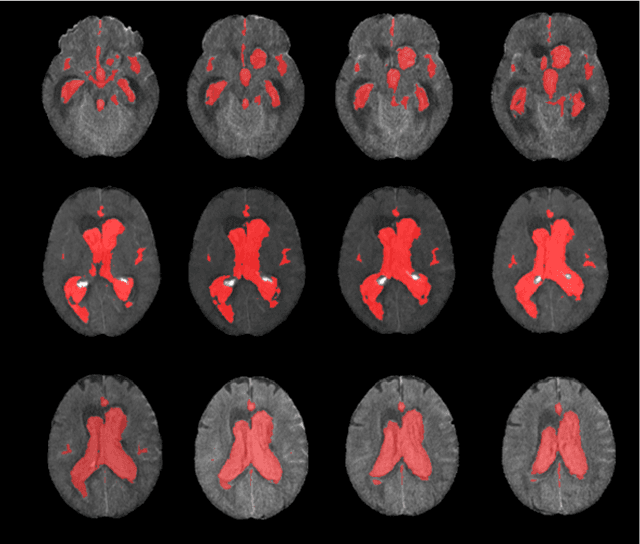

Abstract:Accurately assessing tumor removal is paramount in the management of glioblastoma. We developed a pipeline using MRI scans and neural networks to segment tumor subregions and the surgical cavity in postoperative images. Our model excels in accurately classifying the extent of resection, offering a valuable tool for clinicians in assessing treatment effectiveness.